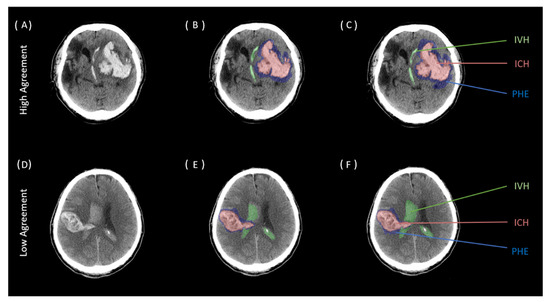

| Intraclass Correlation | ||||

|---|---|---|---|---|

| Region | ICC * | 95% Lower CI | 95% Upper CI | p-Value |

| ICH (n = 100) | 0.997 | 0.996 | 0.998 | <0.001 |

| PHE (n = 100) | 0.980 | 0.971 | 0.987 | <0.001 |

| IVH (n = 100) | 0.995 | 0.992 | 0.996 | <0.001 |

| Interclass Correlation | ||||

| ICH (n = 100) | 0.998 | 0.993 | 0.997 | <0.001 |

| PHE (n = 100) | 0.886 | 0.760 | 0.938 | <0.001 |

| IVH (n = 100) | 0.979 | 0.984 | 0.993 | <0.001 |